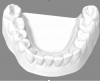

At the same office visit, the patient's records with photographs, digital scans (Figure 7 and Figure 8), and periodontal health evaluation were uploaded and submitted through the clear aligner partner company's portal for evaluation by the treating dentists and orthodontists. Subsequently, the patient continued to receive clear aligner treatment with periodic aligner check-in visits via teledentistry from the treating clinician and team member, using the network practice only for hygiene and in-office routine dental examinations.

Fig 8. Digital scan of lower arch.

Figure 8